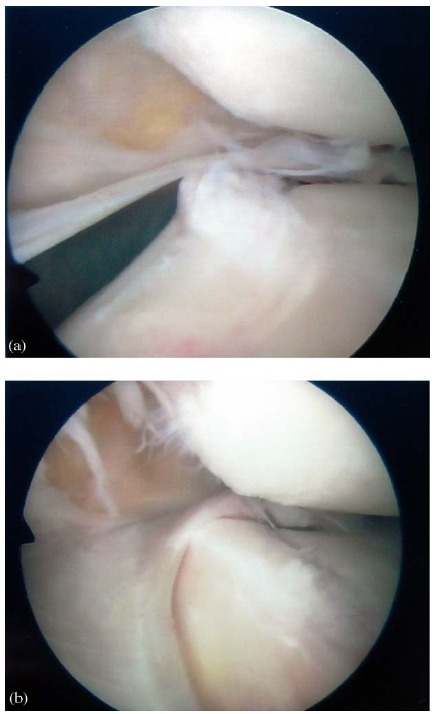

Figure 4 A right medial para-patellar plica viewed from the supero-lateral portal at different degrees of knee

flexion. At 201 (a) the plica bowstrings across the medial femoral condyle, and displaces into the medial gutter at

flexion angles beyond 451 (b). Note the already present degenerative changes affecting the underlying condylar

cartilage.